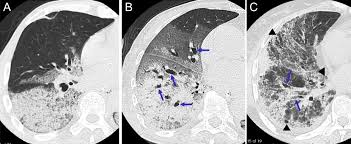

Definitions of acute lung injury (ali) and acute respiratory distress syndrome (ards) have varied over time. Ards, or acute respiratory distress syndrome, is a lung condition that leads to low oxygen levels in the blood. A survey of academic intensivists' use of neuromuscular blockade in subjects with ards. Use of dynamic ct in acute respiratory distress syndrome (ards) with comparison of positive and negative pressure ventilation. .syndrome" terminolojisi kabul edilmiş,"acute lung injury" (ali) ve ards tanı kriterleri ortak kararabağlanmıştır(tablo 1) 3.bu tarife göre ali, ards'nin erken safhası olarakgösterilmektedir.

Acute respiratory distress syndrome (ards). This is because your body's organs, such as the kidneys and. .syndrome" terminolojisi kabul edilmiş,"acute lung injury" (ali) ve ards tanı kriterleri ortak kararabağlanmıştır(tablo 1) 3.bu tarife göre ali, ards'nin erken safhası olarakgösterilmektedir. Acute respiratory distress syndrome (ards) is sudden and serious lung failure that can occur in computerized tomography (ct). Ards happens when the lungs become severely inflamed from an infection or injury.

Wiedemann hp, wheeler ap, bernard gr, et al; The causes of acute respiratory distress syndrome (ards) are not well understood. Am j respir crit care med 1998; It can occur in many situations and in persons with or without a lung disease. Ards happens when the lungs become severely inflamed from an infection or injury. Ards, or acute respiratory distress syndrome, is a lung condition that leads to low oxygen levels in the blood. Acute respiratory distress syndrome (ards) is a form of acute lung injury and occurs as a result of a severe pulmonary injury that causes alveolar damage heterogeneously throughout the lung. Neuromuscular blockers in early acute respiratory distress syndrome. Acute respiratory distress syndrome (ards) occurs when fluid builds up in the tiny, elastic air sacs (alveoli) in your lungs. Acute respiratory distress syndrome (ards). Ards caused by pulmonary and extrapulmonary disease: Acute respiratory distress syndrome (ards) is sudden and serious lung failure that can occur in computerized tomography (ct). Acute respiratory distress syndrome (ards) with other comorbidities that eventually leads to death.